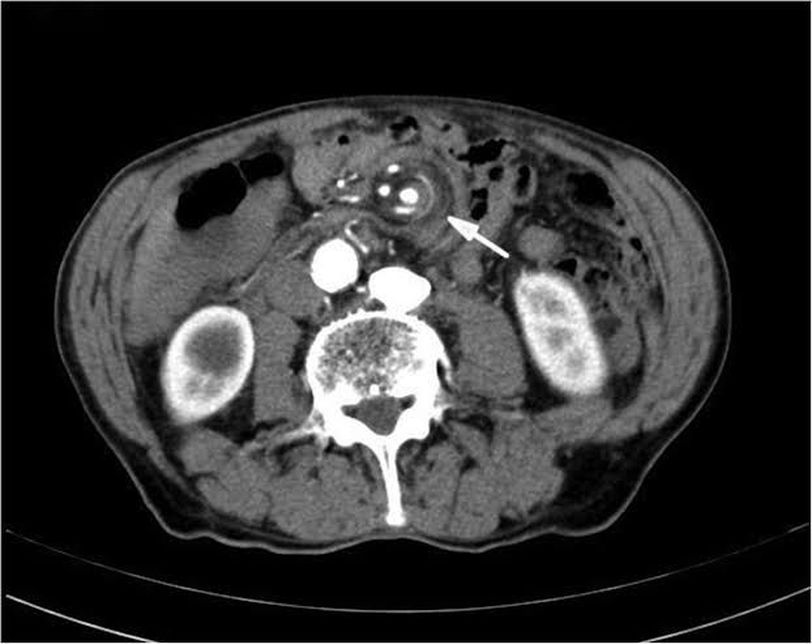

The image shows a classical Whirlpool sign, a radiological finding seen in midgut volvulus. A condition which arises due to the malrotation of intestines. It is one of the important but fatal causes of intestinal obstruction in neonates. The bowel along with mesentery abnormally twists around the superior mesenteric artery, compromising the vascular supply and leading to life threatening complications.